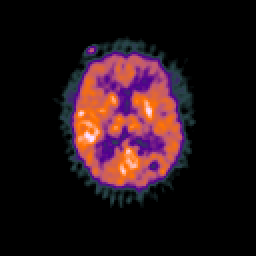

Glioma overlay -- Slice #64

[Home][Help][Clinical] Slice 64